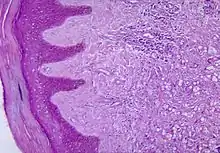

Histopathological changes in the skin seen in lobomycosis. Source: CDC | |

Diagnosis of Lobo's disease is made by taking a sample of the infected skin (a skin biopsy) and examining it under the microscope. Lacazia loboi is characterized by long chains of spherical cells interconnected by tubules. The cells appear to be yeast-like with a diameter of 5 to 12 μm. Attempts to culture L. loboi have so far been unsuccessful.[10]